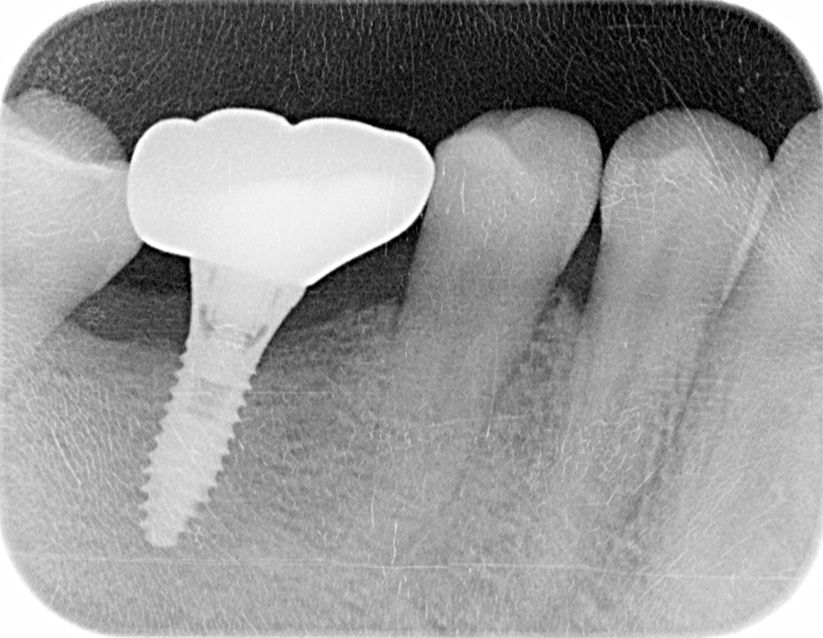

インプラント手術を行いました。

レントゲン画像 -

インプラント手術から3ヵ月後、型どりをして、仮歯を製作しました。